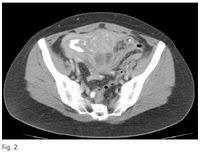

Los abscesos pélvicos son una acumulación circunscrita de pus ysuelen ser en un 90% consecutivos a un divertículo colónico. En el mundo occidental 85 % de los divertículos se localizan en el colon sigmoides, o parte final del intestino grueso antes del recto. Los síntomas suelen ser irregulares, sobre todo en las primeras etapas clínicas. En casi todos los pacientes se observa fiebre recurrente o persistente, que al principio típicamente es intermitente o en espigas y que luego se vuelve más persistente a medida que madura el absceso. Los pacientes que reciben antibioticoterapia pueden no desarrollar mucha fiebre. También puede presentarse íleo paralítico, distensión abdominal, anorexia y en ocasiones vómitos. La antibioticoterapia continua sólo da lugar a un proceso que existe enforma latente durante muchas semanas y dificulta el diagnóstico. En el examen abdominal del absceso pelviano hay pocos síntomas o signos físicos, a menos que el absceso afecte a la pared anterior del abdomen. El paciente se queja de dolor mal localizado y vago en los cuadrantes abdominales inferiores. La irritación de las vías urinarias y del recto produce sensación de urgencia para orinar y polaquiuriao diarrea y tenesmo. Los abscesos generalmente son polimicrobianos. Las acumulaciones de pus localizadas en la pelvis son los abscesos intraabdominales más fáciles de diagnosticar. Por lo general pueden palparse de manera directa mediante el tacto rectal o vaginal. El absceso pélvico típico sobresale como una masa dolorosa hacia la pared rectal anterior. Es importante distinguir entre una masa inflamatoria que afecta a los órganos pélvicos y un verdadero absceso pélvico. La TAC es el estudio radiológico más útil para el diagnóstico de un absceso en lo que se refiere a especificidad, sensibilidad y exactitud. Combinada con la ultrasonografía, permite diagnosticar con precisión más del 90% de los casos. Los problemas que se han informado están relacionadas con la dificultad para distinguir tumores, hematomas, quistes y seromas, los cuales semejan abscesos, aunque con la diferenciación de intensidades y contrastes por medios electrónicos y con la utilización de la resonancia magnética quedan casi perfectamente diferenciados. El tratamiento de inicio de una masa pélvica Abscedada esantibioticoterapiay drenaje, mas biopsia y en caso de ser cancerígeno se extirpa el segmento de colon afectado por el tumor y empalme de los extremos que han quedado separados. La colectomía debe incluir los ganglios linfáticos que recogen el drenaje linfático del segmento de colon afectado para así incluir en la pieza los ganglios afectados si los hubiese. Según el análisis de la pieza extirpada y el número de ganglios afectados se realizará posteriormente tratamiento adyuvante con quimioterapia.